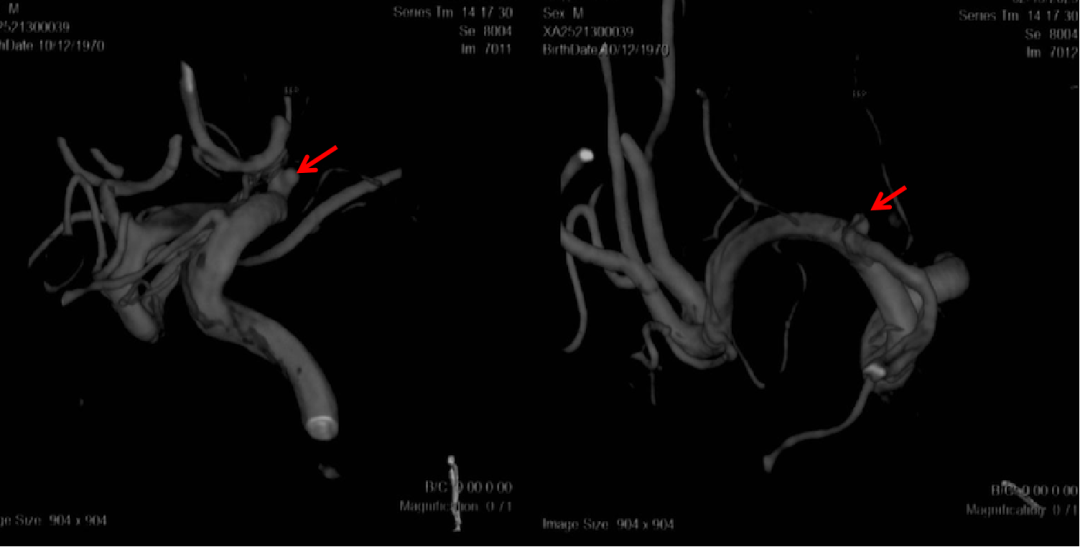

术前外院 DSA 2025-02

箭头所指右侧A1微小动脉瘤

工作位正位造影(图片)

工作位侧位造影(图片)